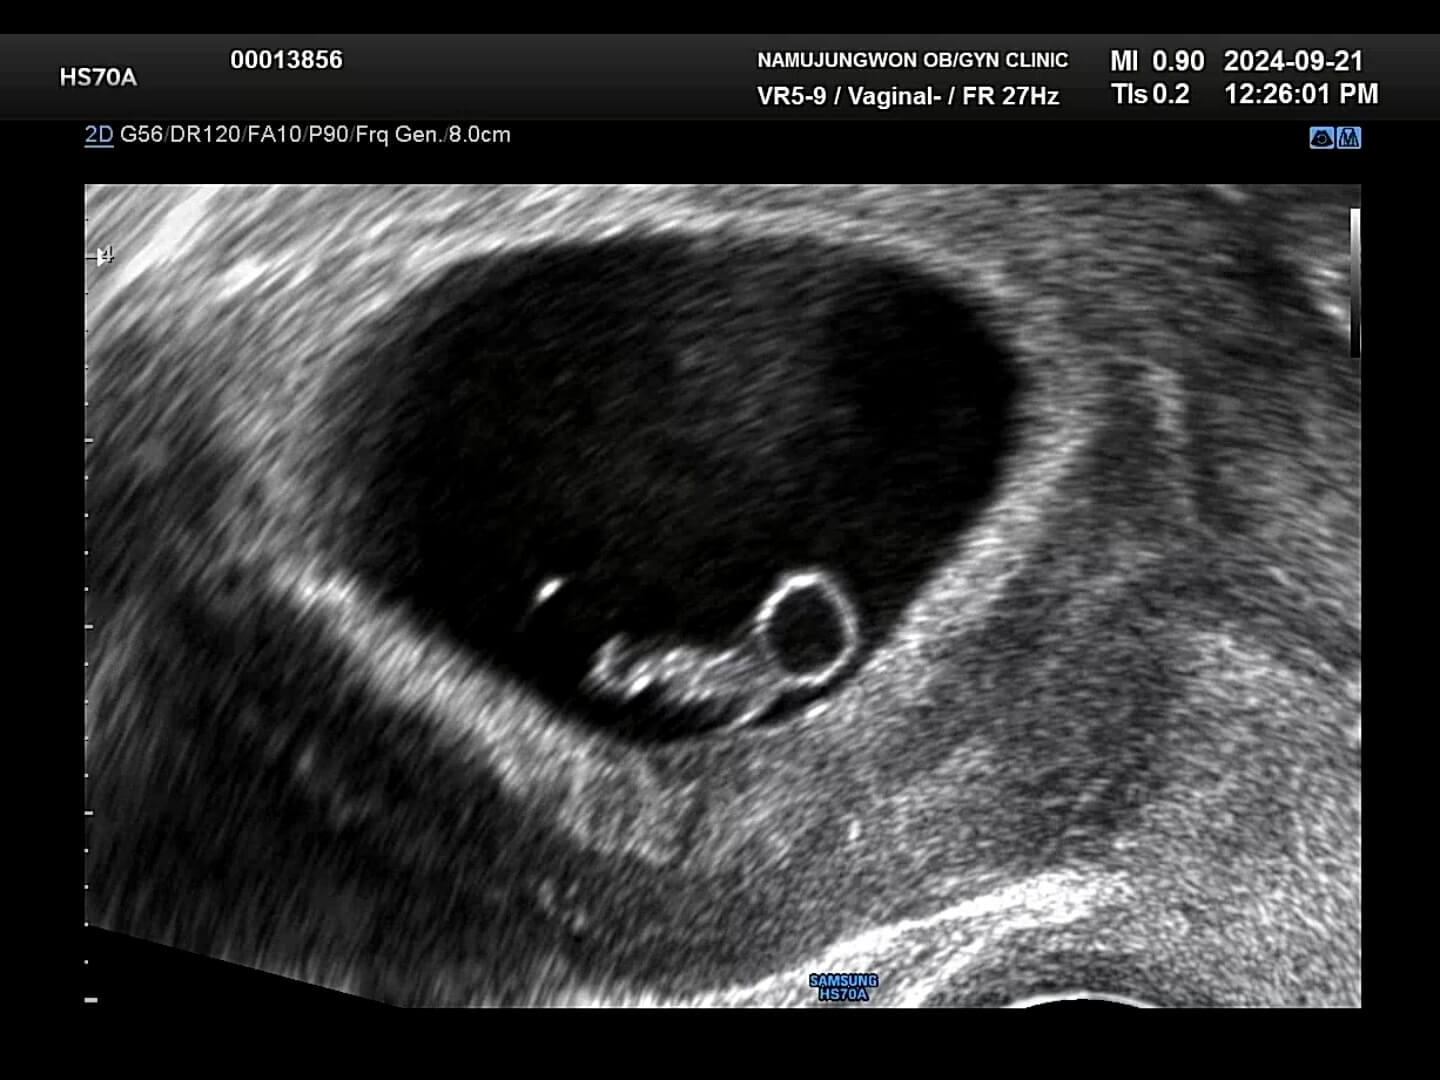

7주차-초음파 그래도 병원에 가서 아기 모습을 보니 너무 신기하고 귀여웠어요. 7주차되는 날 사진인데, 저 동그랗게 보이는게 난황이고 옆에 보이는게 배아라고 하시더라구요. 배아는 난황에 있는 영양분을 섭취하면서 무럭무럭 자라난다고 합니다!